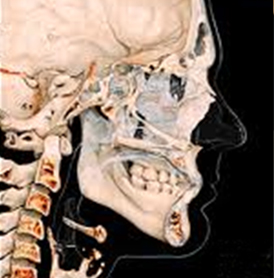

기존의 평면적이었던 X-ray나 파노라마 보다 더 정확하고 더 정밀한

3D CT를 이용하여 치아 뿌리의 상태, 위치, 이동 가능량, 잇몸뼈 등

치아와 잇몸 상태 뿐만 아니라 얼굴 골격까지 진단하여 오차없고 섬세한 치료계획을 수립합니다.